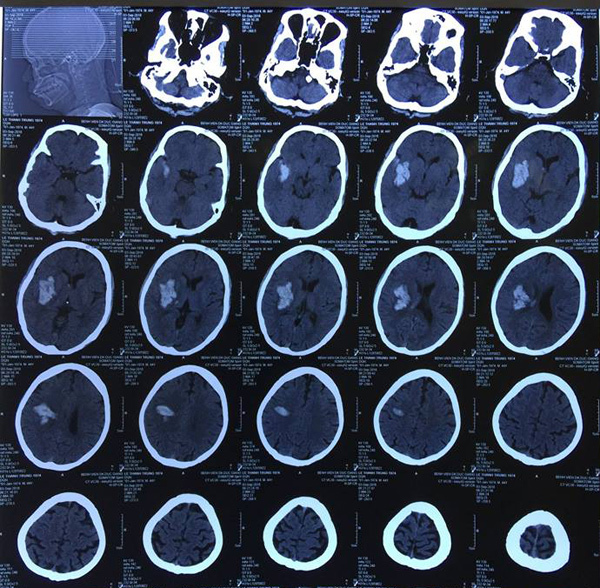

Cắt phăng mảnh sọ cứu sống bệnh nhân chảy máu não ồ ạt

Khối máu tụ trong não bệnh nhân không ngừng lan rộng, buộc bác sĩ phải mở hộp sọ để cứu bệnh nhân.